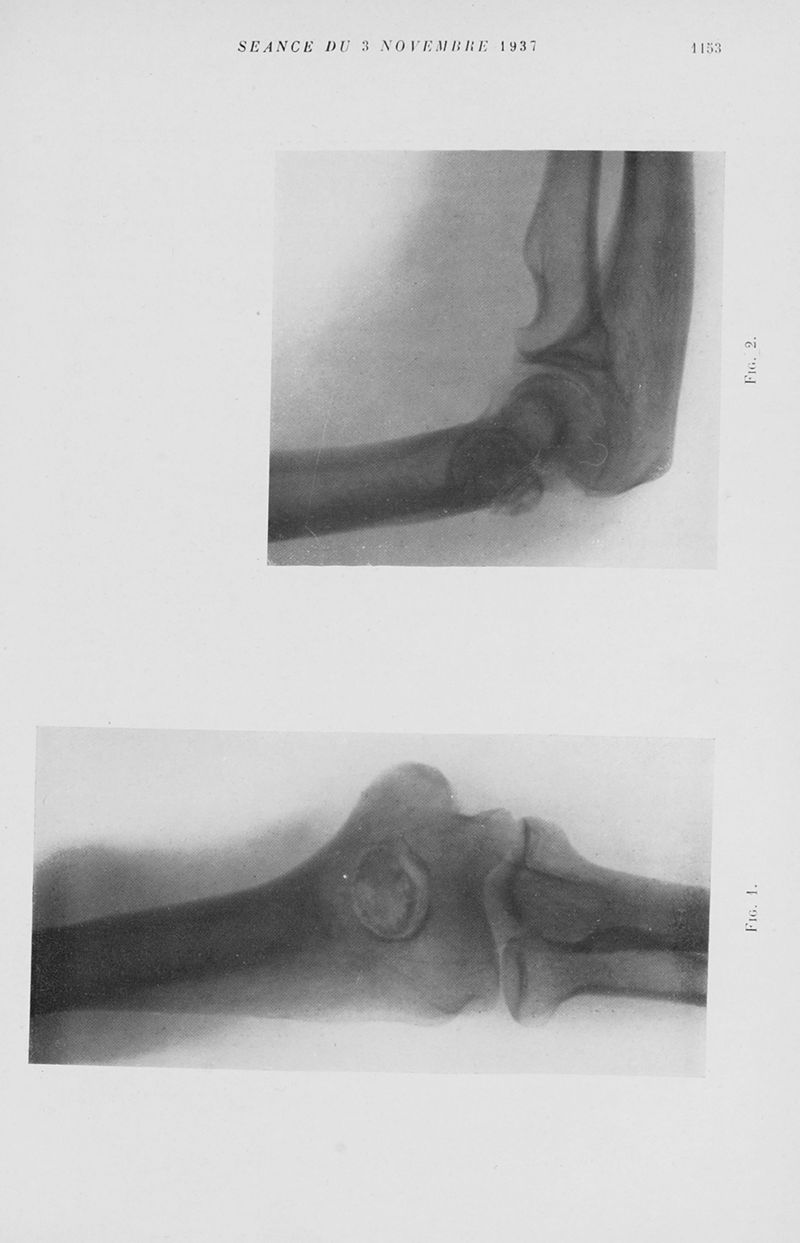

Mémoires de l'académie de chirurgie

Tome 63, 1937. - Paris : Masson, 1937.